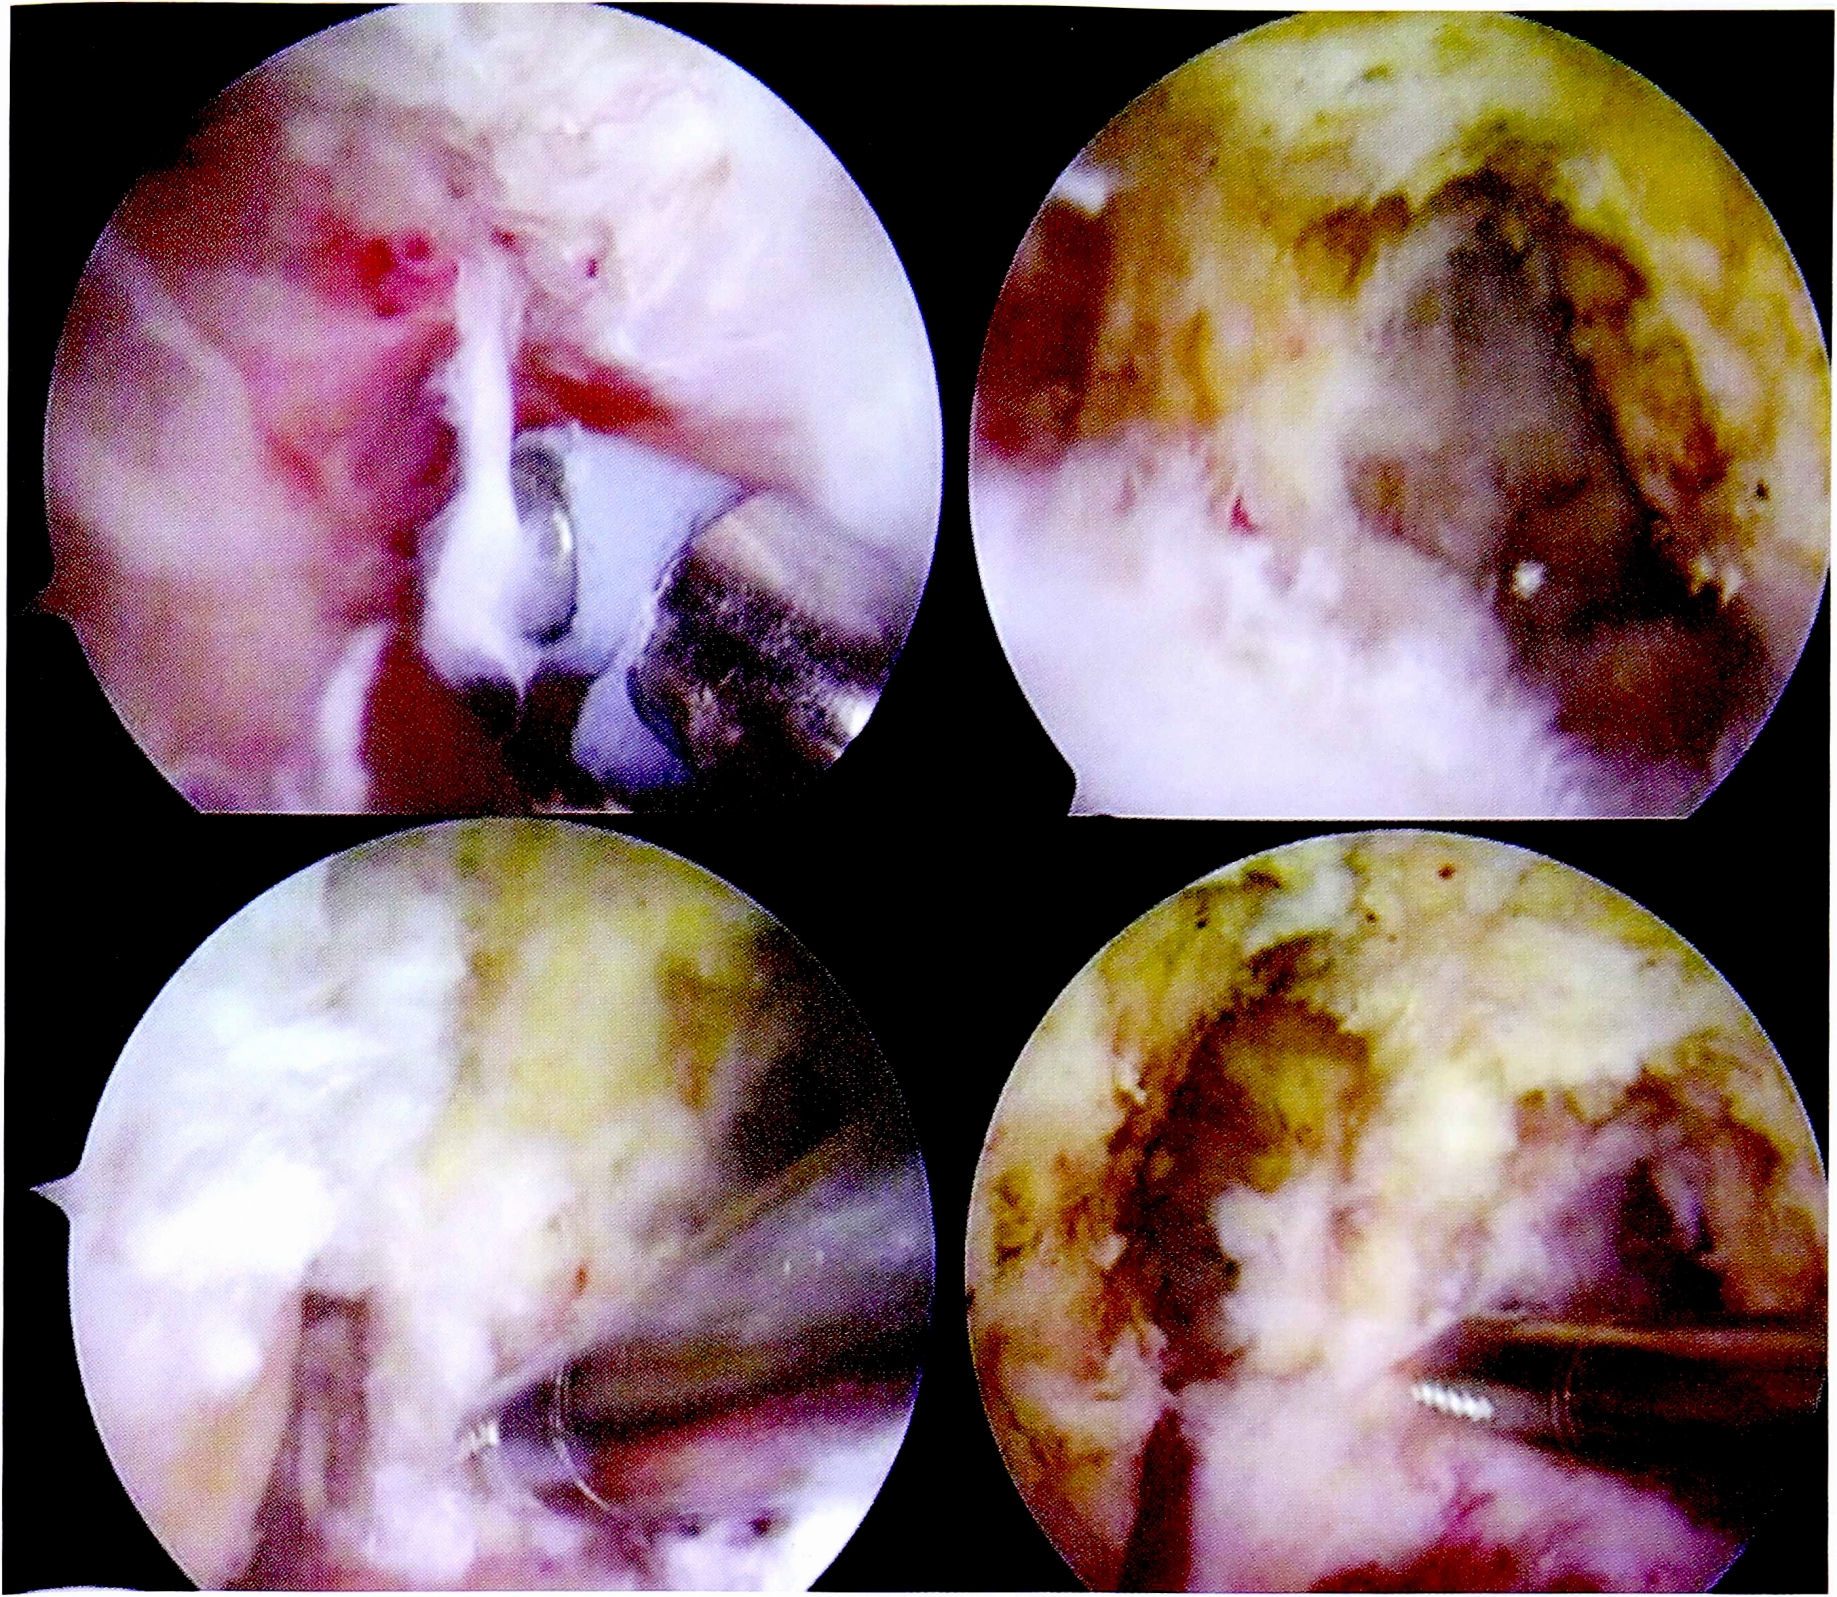

Следующим этапом осуществлялось иссечение рубцовой ткани и фрагментов поврежденных крестообразных связок в межмыщелковом пространстве. Особое внимание уделялось визуализации заднего отдела сустава и заднего межмыщелкового пространства вследствие обязательного формирования дополнительного заднемедиального порта (рис. 3).

Рис. 3. Дебридмент, резекция культи ЗКС.

Fig. 3. Resection of PCL fibers, debridment.

Формирование костных тоннелей проводилось с использованием направителей из набора для пластики крестообразных связок. Костный тибиальный тоннель для ЗКС создавался согласно разработанной методике, через латеральный мыщелок, с выходом в зоне задней межмыщелковой ямки на 15 мм ниже щели сустава (рис. 4).

Рис. 4. Артроскопическая картина формирования тибиального костного тоннеля для пластики ЗКС.

Fig. 4. Making of tibial bone tunnel.

Бедренный костный тоннель формировали согласно анатомическому положению нативной ЗКС — в положении «1,5—2 ч» (для правого коленного сустава), на 3-4 мм кзади от заднего края хряща мыщелка бедренной кости (рис. 5).

Рис. 5. Артроскопическая картина формирования феморального костного тоннеля для пластики ЗКС.

Fig. 5. Making of femoral bone tunnel.

Предварительно измеренные и подготовленные сдвоенные аллогенные сухожилия последовательно проводились в костные тоннели (рис. 6).

Рис. 6. Протягивание и установка аллотрансплантата ЗКС через костные тоннели.

Fig. 6. Positioning of the PCL allograft through the bone tunnels.

После проведения и фиксации на бедренной кости трансплантата ЗКС формировались костные тоннели для пластики ПКС. Использовались стандартная транстибиальная методика и набор направителей для ее выполнения (рис. 7).

Рис. 7. Артроскопическая картина основных этапов пластики ПКС.

Fig. 7. Main stages of ACL plasty.